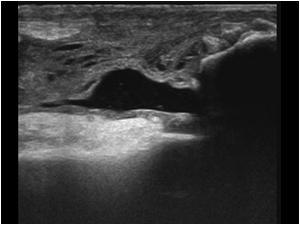

Ultralyd er god til at verificere diagnosen:

Kan laves dynamisk, hvor knæet bevæges samtidigt.